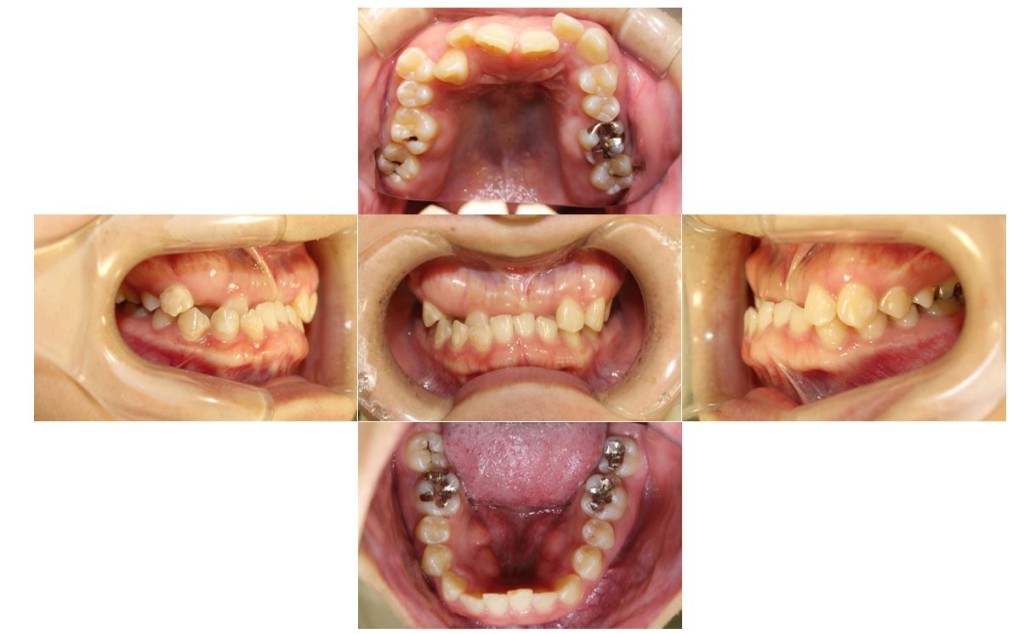

当院の症例

| 主訴 | ずっと気になっていた見た目、噛み合わせを含めて受け口を治したい。期間はかかってもいいので、外科手術をしないで歯列矯正だけで改善したい。 |

| 治療期間 | 3年6ヶ月40回 |

| 抜歯 | 非抜歯 |

| 矯正の装置 | 裏側矯正から治療途中に表側矯正へ変更 |